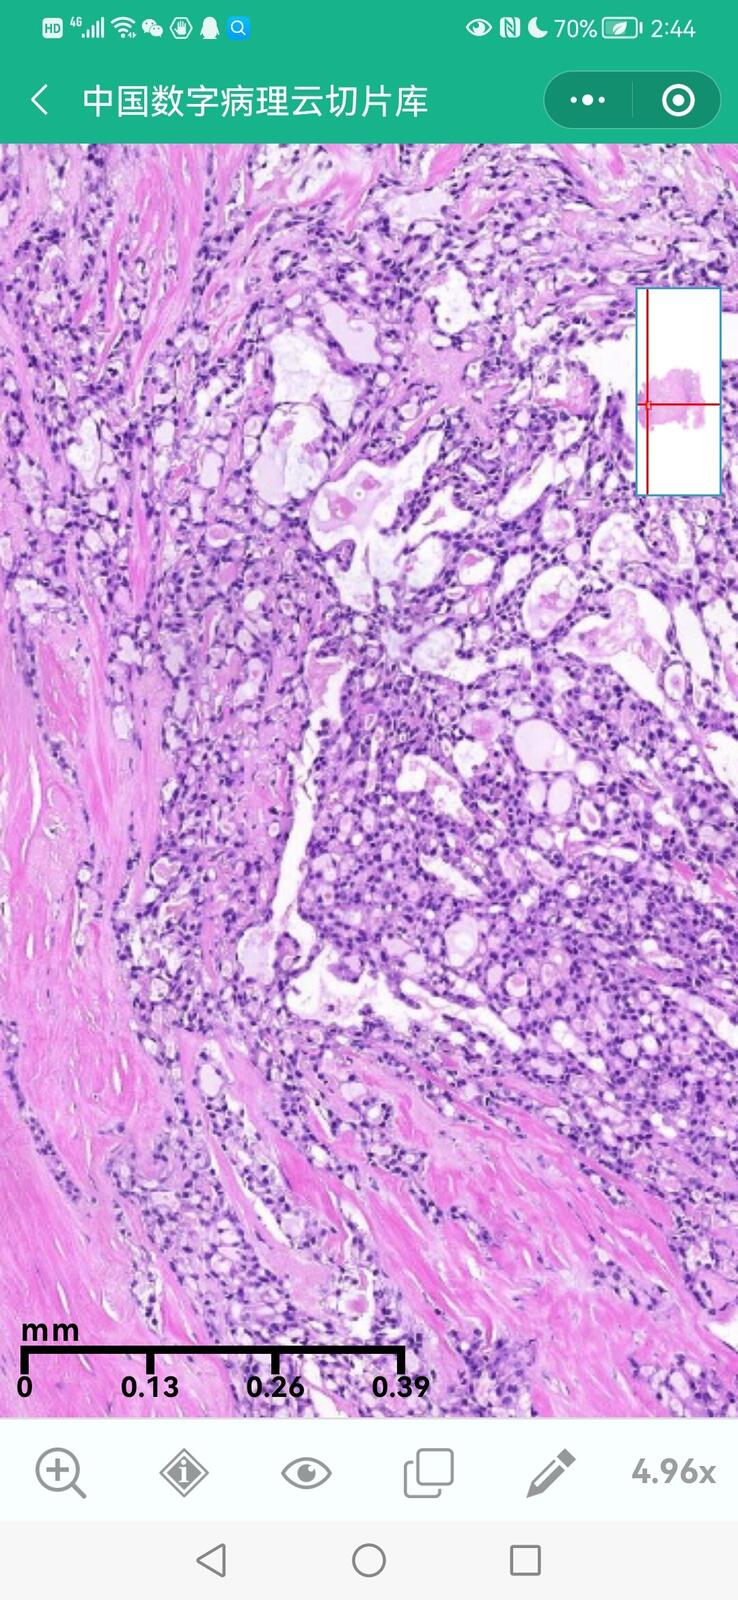

乳腺黏液性囊腺瘤伴导管内癌

乳腺分泌性癌(29岁)